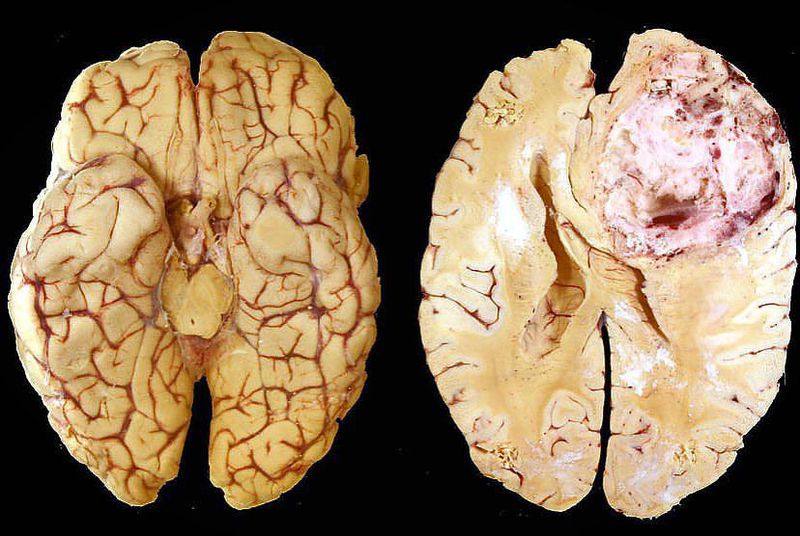

Glioblastoma multiforme is a grade IV astrocytoma; they are therefore generally aggressive, largely resistant to therapy, and have a corresponding poor prognosis. It represents the most common and malignant among glial tumors. These tumors are distinguished from anaplastic asteocytomas by the presence of endothelial proliferation of necrosis. Gross specimens typically show discoloration and cystic changes that result from hemorrhage and necrosis. Glioblastomas are typically poorly-marginated, diffusely infiltrating necrotic masses localised to the cerebral hemispheres. The supratentorial white matter is the most common location. These tumors may be firm or gelatinous. Considerable regional variation in appearance is characteristic. Some areas are firm and white, some are soft and yellow (secondary to necrosis), and still other are cystic with local hemorrhage. They have a significant variability in size from only a few centimeters to lesions that replace a hemisphere. Infiltration beyond the visible tumor margin is always present. The cause of most cases is unclear and symptoms vary among patients and usually includes headaches, nausea, vomiting, stroke-like symptoms, slow progressive neurologic deficit (motor weakness), seizures, and papilledema, many of which are indicative of increased intracranial pressure, most likely due to a space-occupying brain lesion. Furthermore No current treatment is curative. Biopsy and tumor debulking with postoperative adjuvant radiotherapy and chemotherapy (temozolomide) are the most commonly carried out treatment. Newer therapies include antiangiogenesis (e.g. bevacizumab) and immunotherapy.